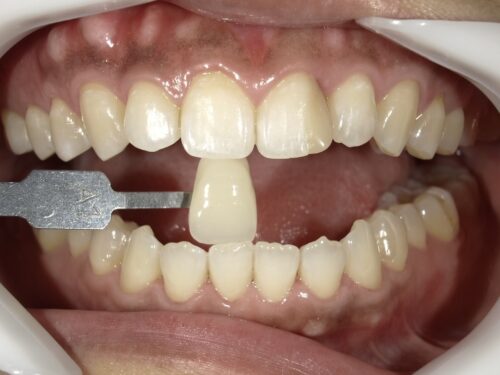

こちらがホワイトニング後の写真です。

A1という色と同じくらい歯が白くなりました。

するとどうでしょう。

古くなった詰め物の色が最初よりも、より際立ってしまっているのがわかります。